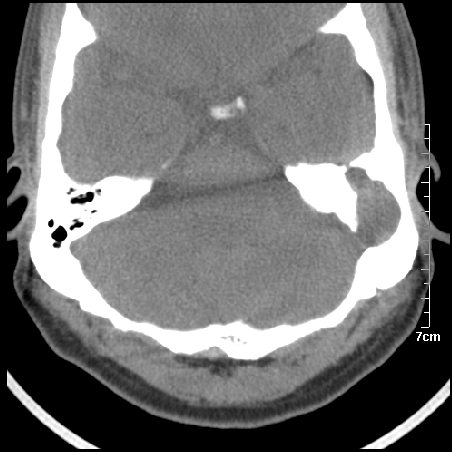

病例1

m/46y 头晕.耳鸣半月余 有乳突炎病史

胆脂瘤是是以鳞状上皮内衬充满角质化碎片的囊,随着角化屑片的不断堆积,肿块逐渐增大,胆脂瘤可为先天性(2%)或后天性(98%)。胆脂瘤有感染史。中耳内的鳞状上皮通常有外耳道的上皮通过一鼓膜的缺损移行至中耳,其他的原因包括鳞状上皮化生。由于欧氏管的功能不全所引起的中耳负压可产生上鼓室鼓膜松弛部的牵引性开袋。继而发展成胆脂瘤。成年人胆脂瘤时乳突常发育差,而儿童常有广泛性乳突气化,这种气化可导致胆脂瘤的更广泛的乳突扩散。后天性胆脂瘤患者大多数存在骨质破坏。

松弛部胆脂瘤有中央性穿孔或后上部牵引口袋所致。紧张部胆脂瘤经常侵蚀听小骨并引起传导性耳聋。

中耳胆脂瘤有两个重要并发症:一是面神经管的水平段受暴露,二是外侧半规管受侵蚀产生瘘管。面神经在ct上难以显示或不可能显示,除非其周围有空气包绕或有良好轮廓的骨性覆盖。胆脂瘤还可合并感染,产生于急性中耳炎.乳突炎所描述的那些合并症。